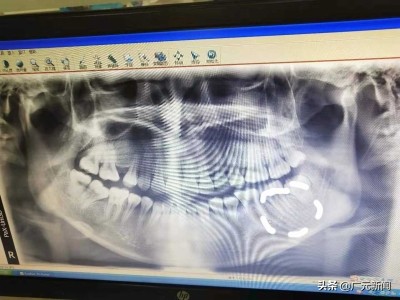

母女士进行根管治疗的具体位置 母女士供图

昨日,市民母女士向广元晚报官方微博反映,近日她在南河某牙科诊所进行根管治疗时,医生将一个针头断在左侧下牙根管治疗处,她认为属于医疗事故。

到医院后,经过医生检查,被告知母女士根管治疗处有一个断折的针头残留。得知这个消息后,母女士来到了牙科诊所讨要说法,她觉得牙科诊所也未主动告知针头断折的情况,未尽到告知义务。